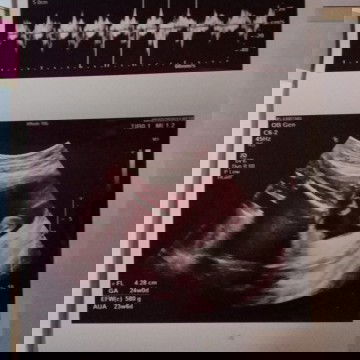

#Nanya bun aman gak sih buat dede nya keseringan di usg